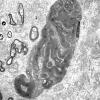

PERIPHERAL NEUROPATHY

0 PNS ARTIFACTS (5)